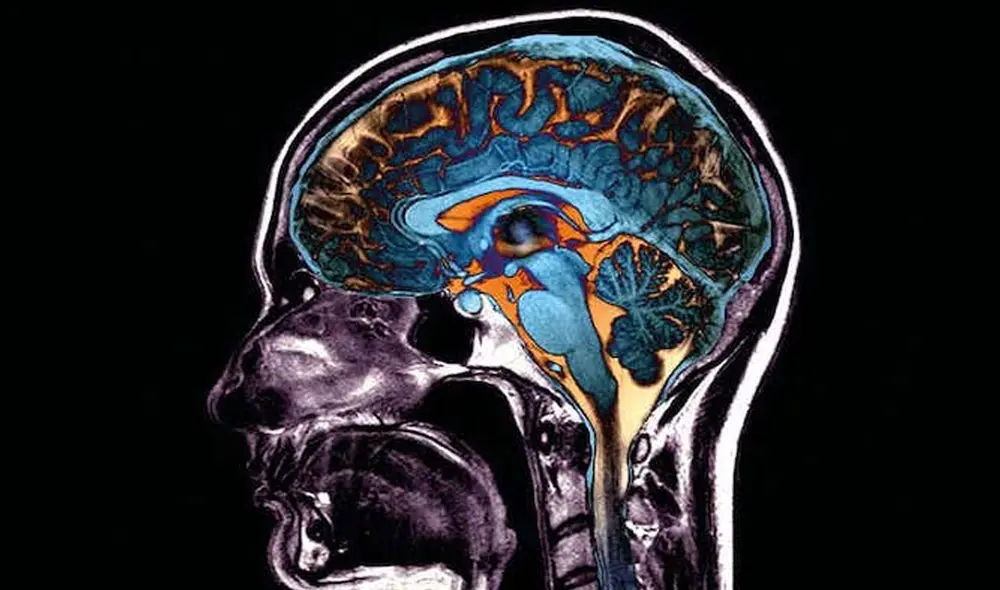

Cómo el coronavirus causa daños en el cerebro sin siquiera infectarlo

Los científicos encontraron áreas dañadas en los cerebros de los fallecidos por COVID-19 a pesar de que no había rastros del virus en las células de este órgano.

La posibilidad de que el SARS-CoV-2 infecte directamente el cerebro ha sido un tema de debate entre los científicos, pero un nuevo estudio asevera que no lo hace, aunque el virus sí puede causar importantes daños neurológicos.

Una investigación que publica la revista Brain y ha sido liderada por el Centro Médico Irving de la estadounidense Universidad de Columbia analizó autopsias de fallecidos por COVID-19 y no pudo encontrar ningún signo del virus en el interior de las células cerebrales.

Sin embargo, los científicos sí observaron “muchos cambios patológicos” en los cerebros, lo que podría explicar por qué los enfermos graves experimentan confusión, delirio y otros efectos neurológicos y por qué los casos leves pueden experimentar niebla cerebral durante semanas y meses, según James Goldman, al frente del estudio.

La investigación sugiere que los cambios neurológicos que suelen darse en estos pacientes se pueden deber a la inflamación desencadenada por el virus en otras partes del cuerpo o en los vasos sanguíneos del cerebro.